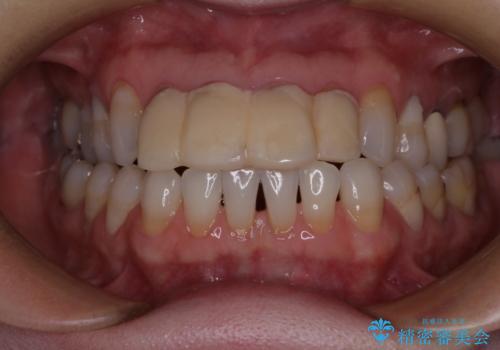

- 自宅近くの歯科医院にて前歯の詰め物が外れたことを機会に、オールセラミッククラウンへの変更を決断して4歯を仮歯に替えたものの、あまりに汚くて恥ずかしいとのことで来院された患者様です。

歯の形成量は不十分で形態は不自然、境目は不適で歯肉が腫れていたため、新しい仮歯に替えた後に歯肉の腫れが引くのを待ち、オールセラミッククラウンにて補綴することとしました。